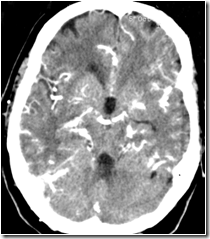

Clinical finding: Acute left hemiparesis.Perfusion CT: Right cerebral infarct.